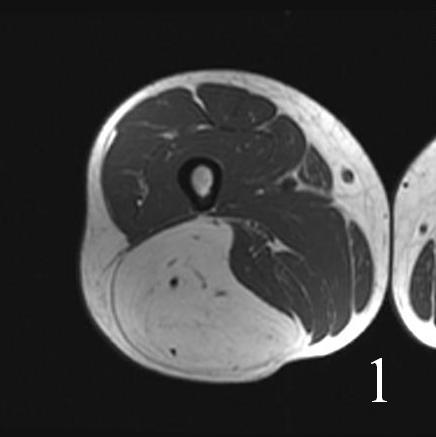

• High signal intensity similar to fat on T1W and T2W (Fig. 1 and 2)

Fig. 1-2 MRI of lower extremity hibernoma (Fig. 1 and Fig. 2) shows similar signal intensity to subcutaneous fat fat on different sequences.